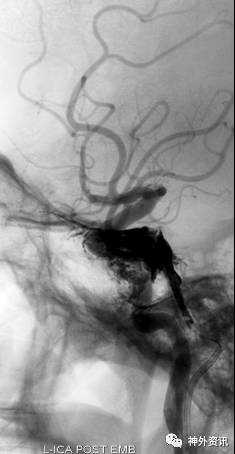

海绵窦区硬脑膜动静脉瘘,海绵窦下外侧干超选栓塞